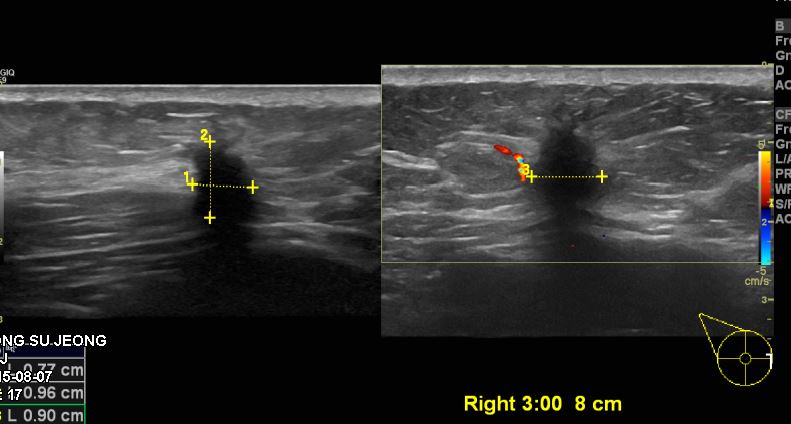

상기환자 60대 여자분으로 우측유방에 10일전부터 만져지는 멍우리있어 본원에서 우측 3시방향에 8cm 떨어진곳에 의심스러운 혹 조직검사시행하였으며 우측유방에 침윤성유관암진단받으셨습니다.